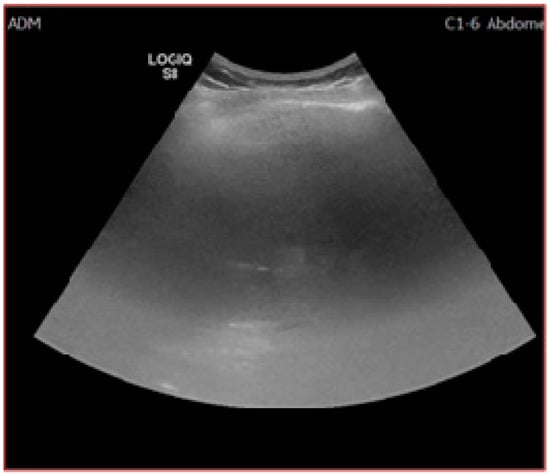

As reported by a recent quality assessment study [] only 66.5% of the reviewed US exams were deemed as “definitely adequate”, which obviously leaves significant room for improvement. Unfortunately, to this point there are no consensus-accepted benchmarks for an adequate examination, which shifts this discussion from the field of “evidence-based” to the realm of practice-derived epistemological subjectivism. According to the study, the most common obstacles towards a proper US report were insufficient parenchymal visualization (less than two-thirds) due to poor beam penetration and excessive rib shadowing (Figure 3). Liver heterogeneity and bowel gas affected the examinations to a lesser extent. The most significant predictors for poor quality were in-patient status, male gender, NASH and obesity, alcohol-induced liver disease, and Child–Pugh B and C [].

Figure 3.

Inadequate US examination. Posterior and superior part of the right lobe could not be visualized due to extensive steatosis and rib shadowing.